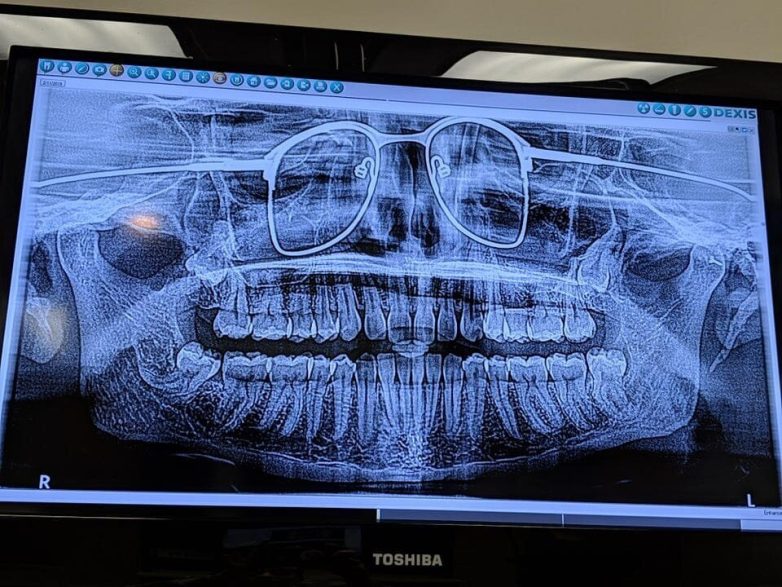

14. Стоматолог забыл попросить меня снять очки на рентгене